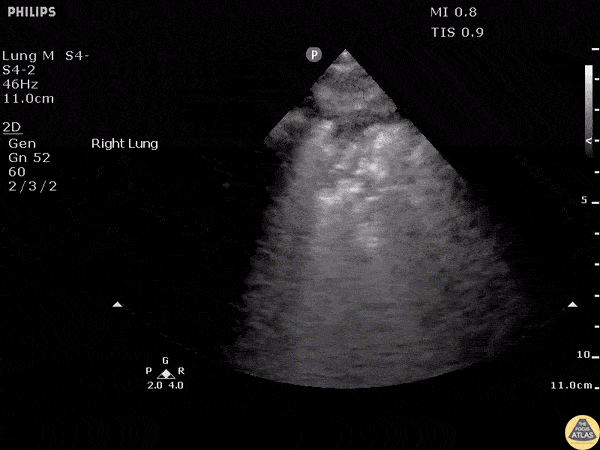

Pulmonary - Pneumonia-Shred Sign

The shred sign is a sign of consolidation in the lung that appears as subpleural hypoechoic areas with an irregular “shredded” border. Image courtesy of Robert Jones DO, FACEP @RJonesSonoEM Director, Emergency Ultrasound; MetroHealth Medical Center; Professor, Case Western Reserve Medical School, Cleveland, OH View his original post here